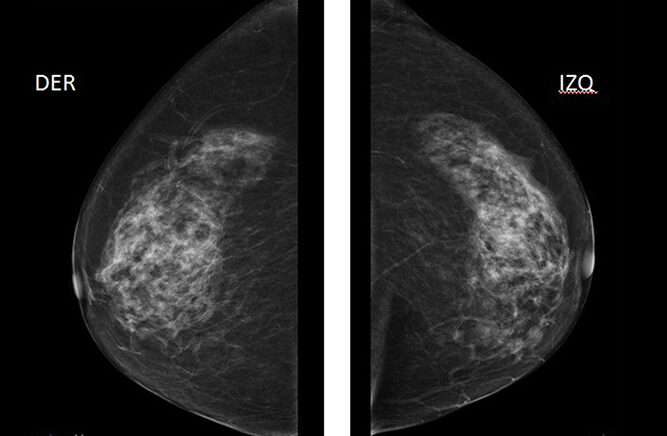

Dado que el cáncer de mama bilateral puede ser un desafío diagnóstico, es crucial que las mujeres que han sido diagnosticadas con cáncer de mama realicen un seguimiento regular para detectar cualquier cáncer oculto en la mama contralateral o en la mama ipsilateral, si ha sido conservada. La mamografía es la herramienta más comúnmente utilizada en estos casos, y debe realizarse antes de iniciar cualquier tratamiento primario para asegurar que no haya un cáncer no detectado en la mama contralateral. Posteriormente, las mamografías deben continuar a intervalos regulares, ya que el riesgo de desarrollar un cáncer en la segunda mama persiste con el tiempo. Este seguimiento regular es esencial para detectar tumores en sus etapas más tempranas y mejorar las perspectivas de tratamiento y supervivencia.